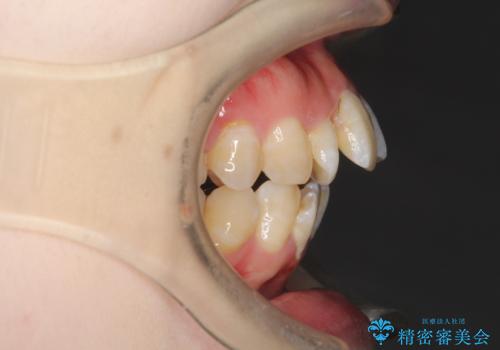

重度のガタガタ ワイヤーによる抜歯矯正

上下の歯に重度のガタガタがあり、前歯が下の歯と咬んでいない状態でした。

抜歯したスペースを使うことで、ガタガタと出っ歯を改善することができました。